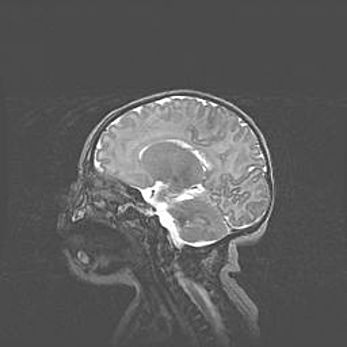

Церебральная ишемия II.

Возраст: 5 дней

Вес: 3400 г

Пол: женский

Окружность головы: 35 см

Срок гестации: 39 недель

Церебральная ишемия – это заболевание, характеризующееся недостаточностью (гипоксией) либо полным прекращением (аноксией) снабжения мозга кислородом по причине закупорки одного или нескольких сосудов. Это приводит к  что метаболическим расстройствам различной степени тяжести в тканях головного мозга, развитию коагуляционных некрозов и гибели нейронов.